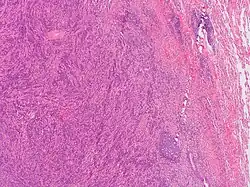

Since plasma cell granulomas have the ability to occur at any site, even though they are uncommon, it should be included in differential diagnostics in regard to plasma cell neoplasms.[3] With granulomas that arise in the mouth, PCGs are commonly misclassified considering the malignancy of the disease due to its aggressive behavior and clinical presentation.[4] Plasma cell granulomas located in the oral cavity have been identified with disruption and damage of surrounding tissues.[4] In comparison, PCGs manifesting in other internal organs are usually secondary findings on radiographic images.[4] Occasionally, plasma cell granulomas are misdiagnosed as malignant lymphoma or malignant plasmacytoma during initial examination due to radiological evidence of its ability to erode and infiltrate bone.[4] Typically, under microscopic analysis, a plasma cell granuloma will display a dense population of morphologically similar plasma cells sporadically mixed together with other inflammatory lymphocytes seen in a storiform orientation of fibrotic connective tissue.[3][4] To avoid the misdiagnosis of a PCG as a plasmacytoma, it should be noted PCGs are formed from typical plasma cells while plasmacytomas consist of both atypical and typical plasma cells.[4] It is imperative that such differentiation between plasma cell granuloma and plasmacytomas are completed prior to informing the patient undergoing clinical examination.[4] The importance of an accurate diagnosis between the two is due to the different prognosis and progression of the mass-forming lesions.[4] While plasma cell granulomas are often found to be benign, plasmacytomas have been associated with a more aggressive and invasive behavior in which they have the ability to transform or evolve into multiple myeloma.[4] One of the most reliable distinguishing factors from plasmacytomas and plasma cell granulomas, is the polyclonality of the plasma cells involved with plasma cell granulomas.[3] PCGs that manifest in the mouth, specifically the gingiva, have been seen to exhibit similar physical characteristics of other conditions such as epulis, fibroma, pyogenic granuloma, and peripheral giant cell granuloma.[4] Histopathological analysis of plasma cell granulomas have been found to be the most precise confirmative diagnosis to distinguish PCGs from other lesional tumors of plasma cell origins.[4]

Analyzing the changes that arise in the tissue associated with the mass-forming lesion has been found to be the most accurate and precise method for confirming the diagnosis of plasma cell granulomas. This can be achieved by taking excision biopsies of the unknown mass for examination.[4] Typically, plasma cell granulomas appear microscopically as a lesional mass consisting of an abundance of plasma cells intermingled among different inflammatory cells set in fibrous connective tissue displayed in a spiral appearance.[3][4] Depending on the location of the plasma cell granuloma, vasculitis can be present but is not considered a confirmatory factor for diagnosis.[3] Kappa/lambda in-situ hybridization is another diagnostic test that needs to be done when trying to characterize the lesion for further confirmation.[3] Common results associated with kappa/lambda in-situ hybridization studies of PCGs are an abundant population of CD138 positive polyclonal plasma cells.[3] If instead, results show monoclonality of plasma cells it is indicative of plasmacytoma.[3]